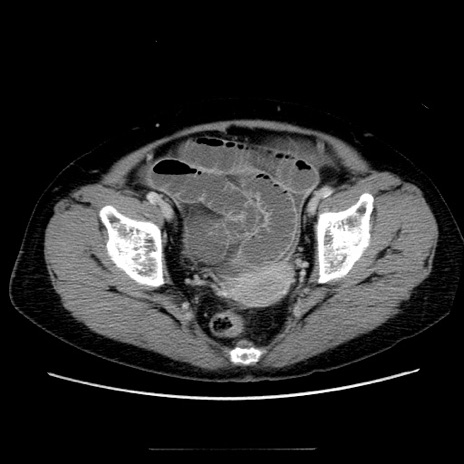

症例5(横断像)

【症例】70歳代女性

【主訴】お腹が張る

【現病歴】1週間くらい前から腹部膨満の自覚あり。昨日夜から増悪したため、本日救急外来受診。

【身体所見】意識清明、BT 36.5℃、BP 165/106mmHg、HR 80bpm、SpO2 98%、腹部:膨満、軟、自発痛・圧痛なし、触診にて不快感あり、腸蠕動音:減弱

【データ】WBC 12600、CRP 1.04